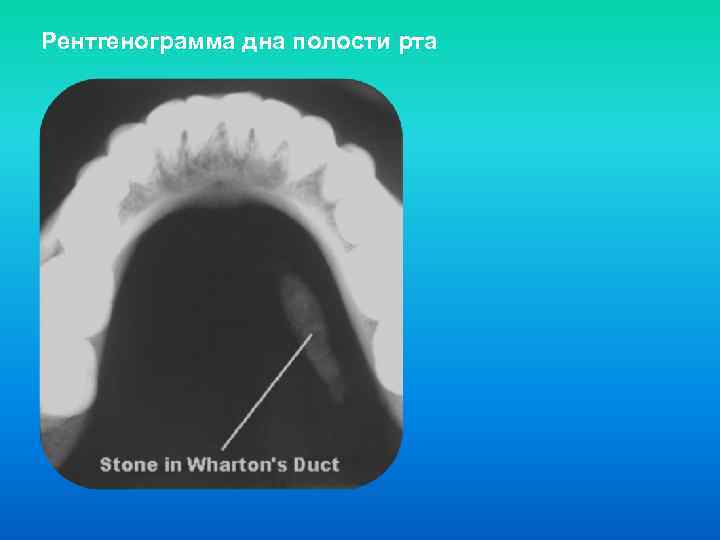

Рентгенограмма дна полости рта

Рентгенограмма дна полости рта